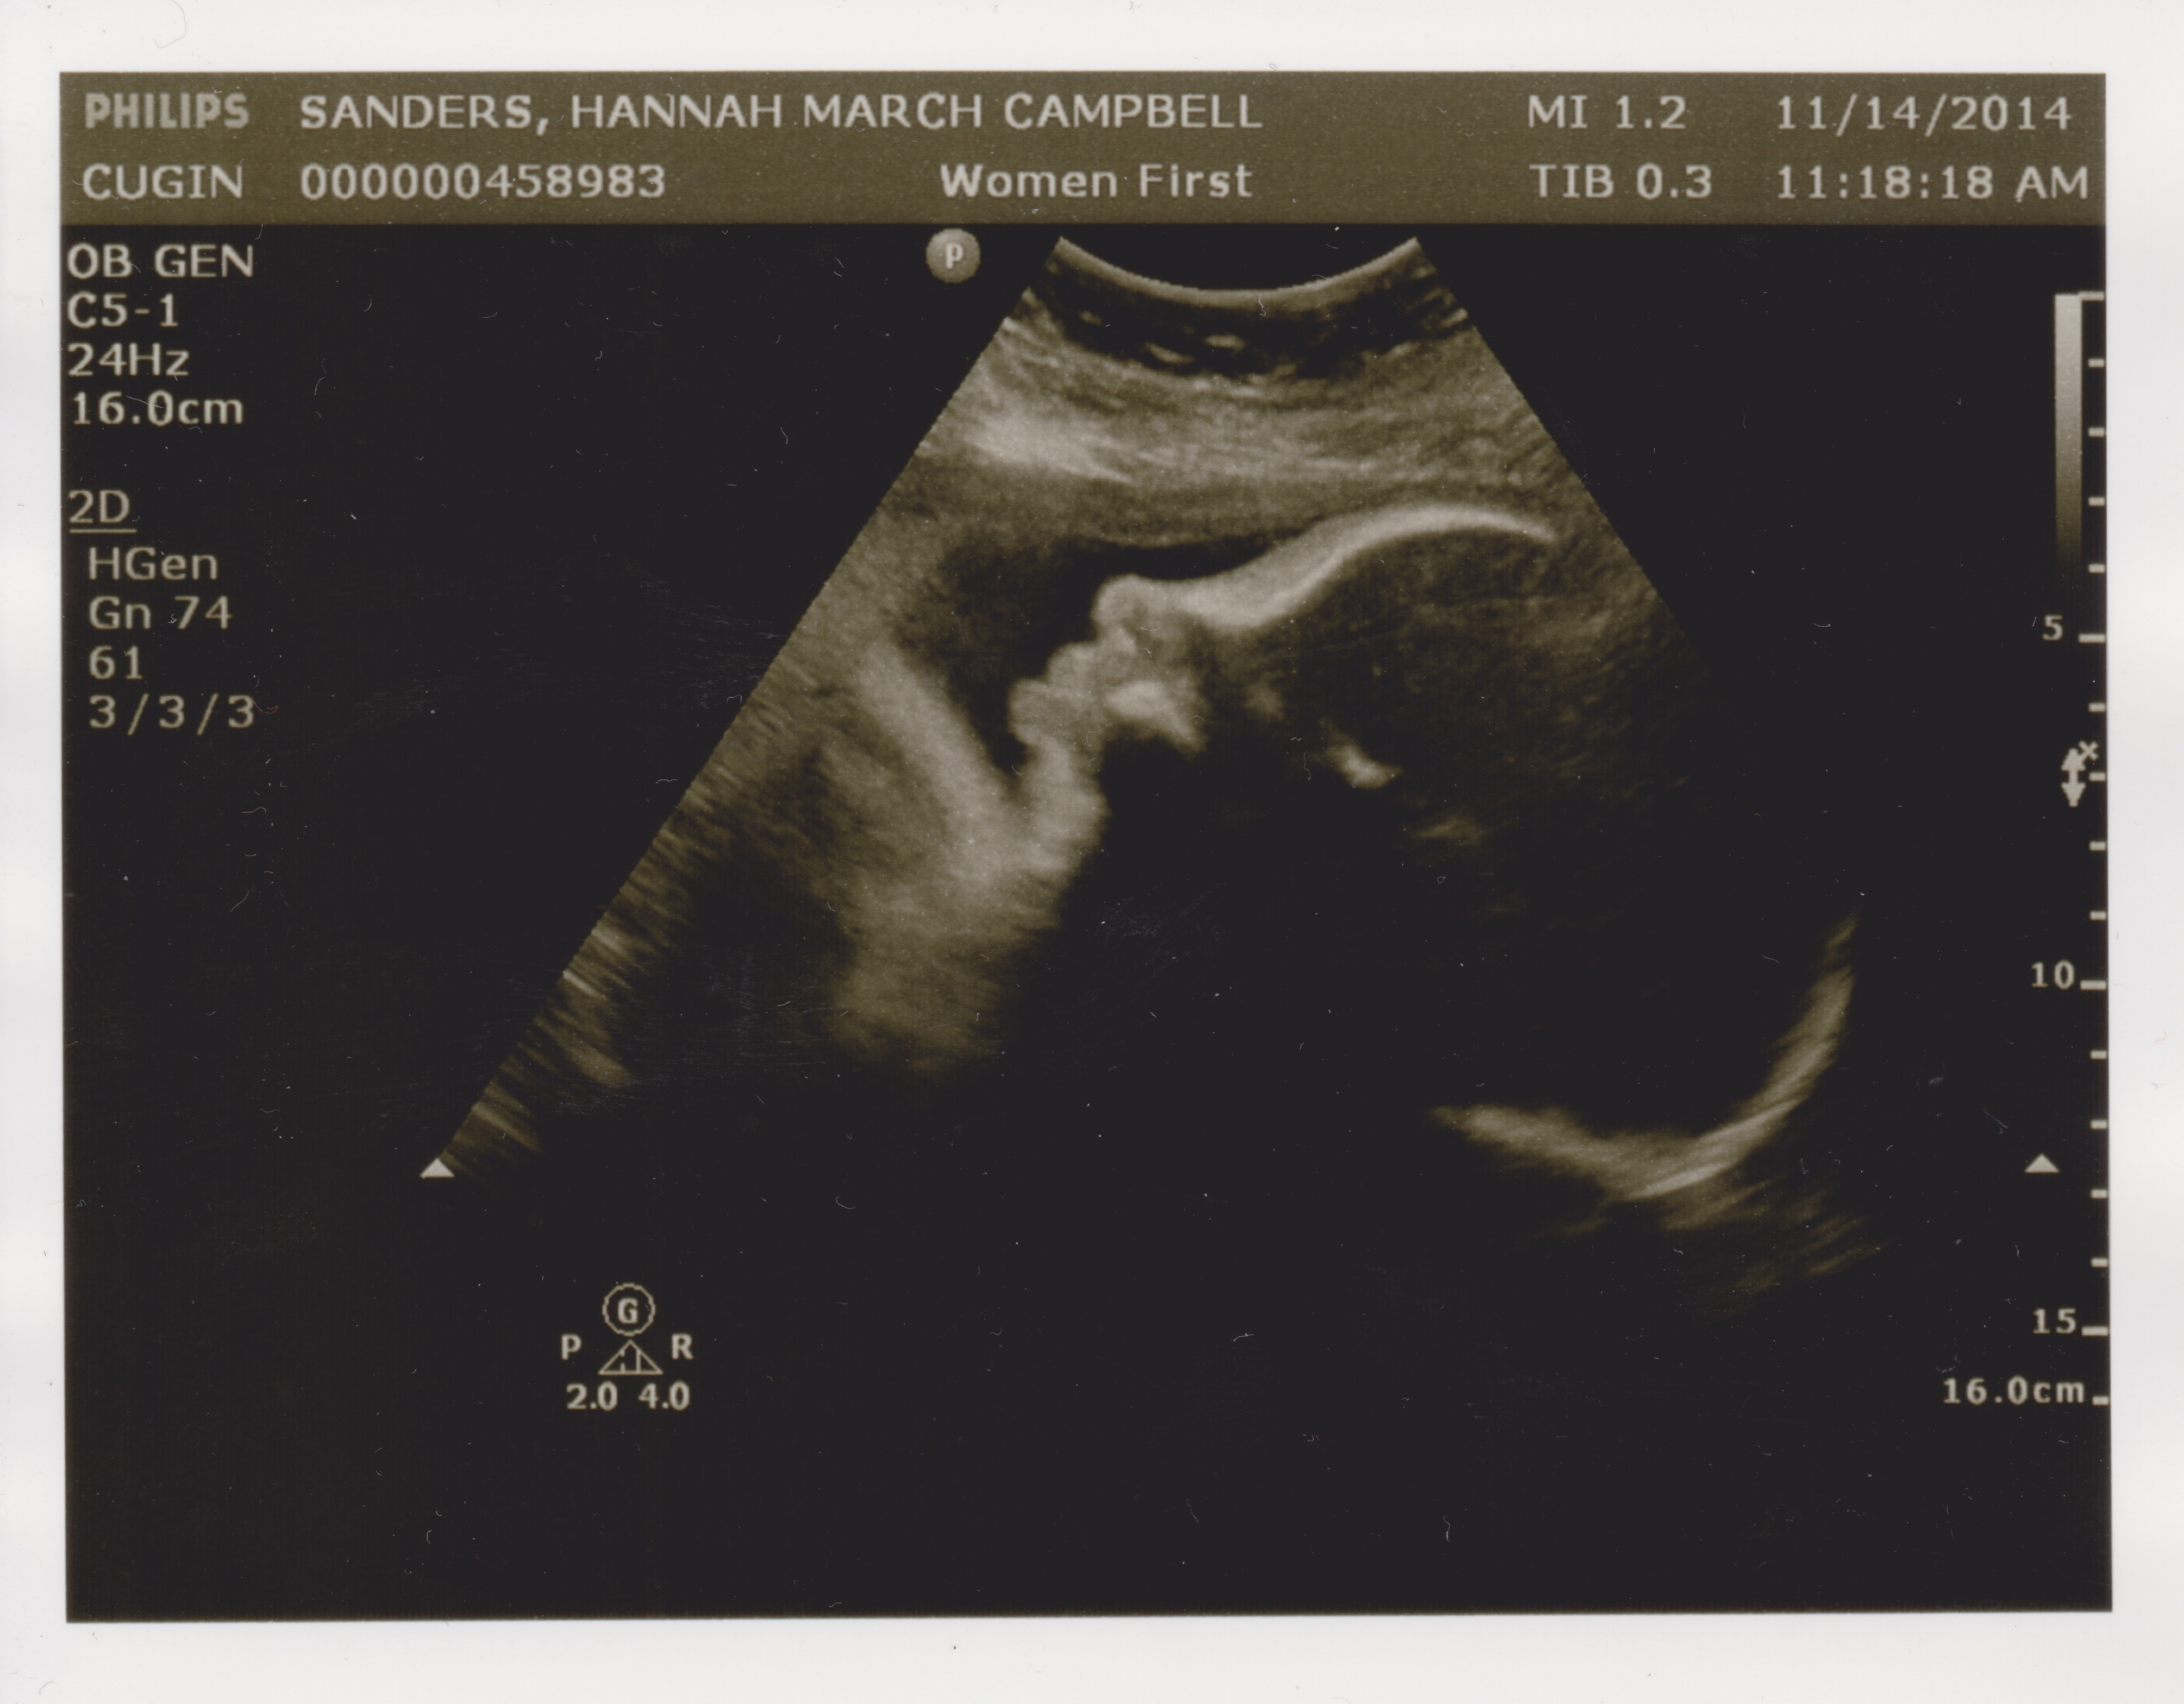

Another Friday, another doctor’s appointment. Today was Hannah’s second ultrasound in as many weeks, to check on the growth rate of the undersized nugget. In the last two weeks it’s gained a little less than half a pound, from 4lb. 5oz. to 4lb. 12oz. That was about a half pound less than the ultrasound tech. was hoping for, but Dr. Cugini doesn’t seem super concerned.

However, the baby is now under the 10th percentile for growth, so in order to prove everything’s OK, a new regimen begins. From here on in it’ll be two visits a week. Once a week we’ll go in for a BPP, an ultrasound that checks for growth and muscle-tone. Later in the week it’s another NST, the dreaded Non-Stress Test, where Hannah has air hockey paddles strapped to her belly for half an hour while the baby’s heartbeat blares like feedback at a death metal concert. Non-Stress indeed!